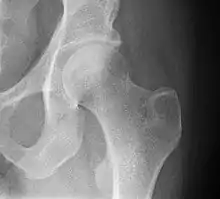

The hip region is located lateral and anterior to the gluteal region, inferior to the iliac crest, and overlying the greater trochanter of the femur, or "thigh bone".[2] In adults, three of the bones of the pelvis have fused into the hip bone or acetabulum which forms part of the hip region.

The hip joint, also known as a ball and socket joint, is formed by the acetabulum of the pelvis and the femoral head, which is the top portion of the thigh bone (femur). It allows for a wide range of movement and stability in the lower body.[3]

The hip joint is a ball and socket synovial joint formed by the articulation of the rounded head of the femur and the cup-like acetabulum of the pelvis.[5] The socket of the acetabulum is pointing downwards and anterolaterally. The socket is also turned such that the outer edge of its roof is more lateral than outer edge of the floor.[5] It forms the primary connection between the bones of the lower limb and the axial skeleton of the trunk and pelvis. Both joint surfaces are covered with a strong but lubricated layer called articular hyaline cartilage.

The cuplike acetabulum forms at the union of three pelvic bones — the ilium, pubis, and ischium.[6] The Y-shaped growth plate that separates them, the triradiate cartilage, is fused definitively at ages 14–16.[7] It is a special type of spheroidal or ball and socket joint where the roughly spherical femoral head is largely contained within the acetabulum and has an average radius of curvature of 2.5 cm.[8] The acetabulum grasps almost half the femoral ball, a grip deepened by a ring-shaped fibrocartilaginous lip, the acetabular labrum, which extends the joint beyond the equator.[6] The centre of the acetabulum (fovea) does not articulate to anything. Instead, it is lined with fat pad and attached to ligamentum teres. The acetabular labrum is horse-shoe shaped. Its inferior notch is bridged by transverse acetabular ligament.[5] The joint space between the femoral head and the superior acetabulum is normally between 2 and 7 mm.[9]